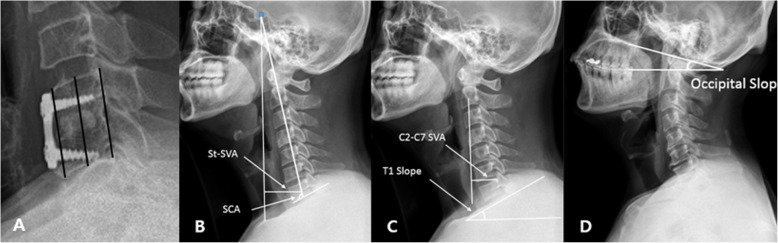

Fig. 3.

A: Subsidence measurements were performed from the anterior, middle, and posterior portions of the vertebral bodies of interest. Subsidence was described as a greater than 3 mm decrease in height of the operative segment between images produced immediately after the operation and those acquired at 2 years follow up. B: The SCA was defined as the angle between the C7 line and the line joining the center of the sellar turcica and the center of the inferior endplate of the C7 body. The center of the St-SVA was defined as the distance between a plumb line from the center of the sellar turcica and the center of the C7 body. C: The C2–C7 SVA was decided as the length from the posterosuperior corner of C7 and the vertical line from the center of the C2 body. The T1 slope was defined as the angle between the upper endplate of T1 and the horizontal line. D: O-s is the angle between the McGregor line and the horizontal line

Radiological evaluation

Preoperative radiologic examination evaluated plain radiographs, computed tomography scans, and magnetic resonance imaging. Plain radiological examinations of the cervical spine were also conducted immediately after surgery and at 2-year follow up for all patients. Cervical alignment was evaluated using the Cobb angle of C2–C7, working the process described by Borden [7]: this angle was made by the lines along the inferior endplate of C2 to the inferior endplate of C7 in the neutral position. Subsidence was decided by measuring the distance from the upper endplate of the upper vertebral body to the lower endplate of the lower vertebral body at the level of the operation. The segmental angle was calculated using the Cobb angle of the adjacent vertebrae in the intervertebral disc involved. The total intervertebral height was decided as the length from the upper endplate of the cephalad vertebrae to the inferior endplate of the caudal vertebrae of the fused segment, which was quantified as the mean value of the height of the anterior and posterior borders [8]. Subsidence was described as a decline in the height of the operative segment greater than 3 mm between immediate images after the operation and those acquired at the last follow up (Fig. 3A). Spino-cranial angle (SCA) was defined as the angle between the C7 line and the line joining the center of the sella turcica and the center of the inferior endplate of the C7 body. The center of the sella turcica – C7 sagittal vertical axis (St-SVA) was defined as the distance between a plumb line hung from the center of the sella turcica and the center of the C7 body (Fig. 3B). The C2–C7 sagittal vertical axis (SVA) was decided as the length from the postero-superior corner of C7 and the vertical line from the center of the C2 body. The T1 slope was defined as the angle between the upper endplate of T1 and the horizontal line (Fig. 3C). Because keeping horizontal gaze is the most important function of the cervical vertebrae, patients maintained a horizontal gaze position during radiologic examination. Occipital slope (O-s) is a postural variable reflecting the position of the skull, and it can reflect the degree of horizontal gaze. O-s represents the angle between the McGregor line and horizontal line (Fig. 3D). We decided the maximum difference in the O-s values at each examination as 2 degrees. Radiological fusion was decided to have occurred when there was ≤2° movement on flexion–extension and/or ≤ 2 mm of movement of the interspinous distance on flexion–extension across the fusion segment [9].